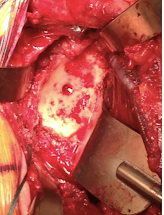

The glenoid was reamed to a diameter of curvature 4-6 mm greater than that of the selected humeral component, preserving as much subchondral bone as possible.